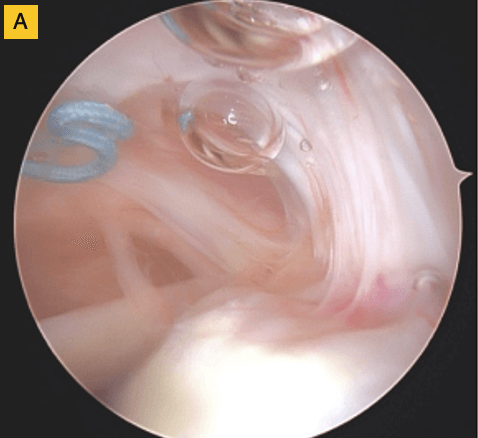

Down the road, this patient was having some bicipital pain, so we took the opportunity to look at the repair visually and performed a biceps tenodesis. You can see in this image, there's cabling of the fibers coming down onto the footprint and you can no longer see the scaffold… it’s been completely incorporated into the repair. For this patient, that was a pretty remarkable event.

(A) Tendon fibers can be seen inserting on to footprint in an organized fashion. Visible, prominent suture easily removed.

(B) BioBrace® well-synovialized and completely incorporated into the rotator cuff with new native tissue in and around the implant.